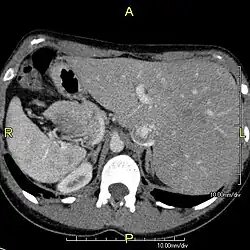

Diagnosis of situs inversus can be made using imaging techniques such as x-ray, ultrasound, CT scan, and magnetic resonance imaging (MRI).[9]

The condition affects all major structures within the thorax and abdomen. Generally, the organs are simply transposed through the sagittal plane. The heart is located on the right side of the thorax, the stomach and spleen on the right side of the abdomen and the liver and gall bladder on the left side. The heart's normal right atrium occurs on the left, and the left atrium is on the right. The lung anatomy is reversed and the left lung has three lobes while the right lung has two lobes. The intestines and other internal structures are also reversed from the normal, and the blood vessels, nerves, and lymphatics are also transposed.

Situs inversus is found in about 0.01% of the population, or about 1 person in 10,000. In the most common situation, situs inversus totalis, it involves complete transposition (right to left reversal) of all of the viscera. The heart is not in its usual position in the left chest, but is on the right, a condition known as dextrocardia (lit. 'right-hearted'). Because the relationship between the organs is not changed, most people with situs inversus have no associated medical symptoms or complications.[1]